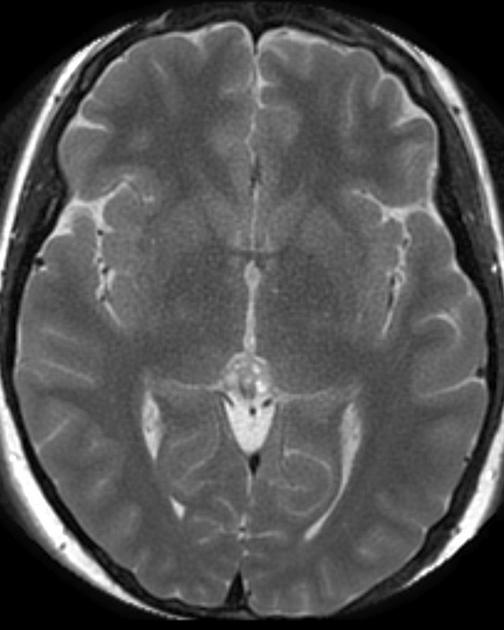

The general workup is MRI with T1/T2 images. Pineoblastomas are generally iso-enhancing on both T1 and T2, but T2 shows cystic components, at times becoming larger than the tumor itself. Surgical resection is treatment which also serves to provide tissue for diagnosis.

Pineocytoma T2